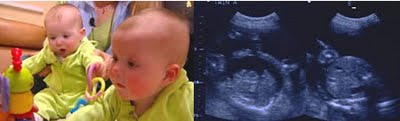

Shannon and Mike Gimbel faced an agonizing choice. Doctors told them one of the twin girls they were expecting needed to be terminated or both would die. Doctors at Swedish Medical Center had diagnosed Gimbel's twins with Twin-To-Twin Syndrome, or TTTS. It is a condition in which the twins are connected by blood vessels. One twin literally drains the life out of the other. Left untreated, there is an 80 to 90 percent chance that one or both will die.Shannon and Mike were struggling with the suggestion to terminate the weaker baby when their physician at Swedish, Dr. Kent Heyborne, approached them with another option. He'd made contact with Drs. Robert Bell and Michael Belfort of St. Mark's Hospital in Salt Lake City, Utah. The Utah surgeons teamed with those at Swedish to perform laser surgery in the womb to cauterize the blood vessels that were connecting, and slowly killing, the twins.Shannon says she remembers holding her breath as a nurse used an ultrasound to listen for heartbeats after the surgery. One, then another. Both girls had made it. Reese and McKenna Gimbel were born at Swedish two months later.